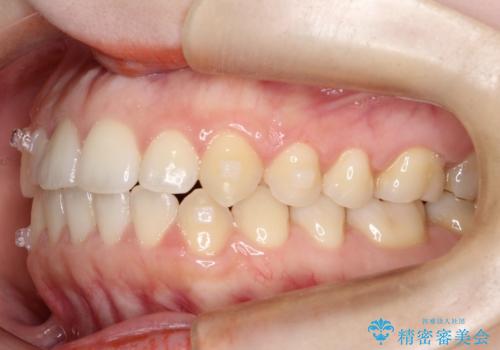

前歯のガタツキ、前歯の噛み合わせ(開咬)をインビザライン治療で治しました

- 前歯のがたつき、噛み合わせが気になるとのことで来院された患者様です。

インビザラインを使用して治療しました。

前歯がしっかり噛んでない状態(開咬)を治すために、前歯にゴムをかける必要があります。ゴムかけは患者様にご協力していただきます。